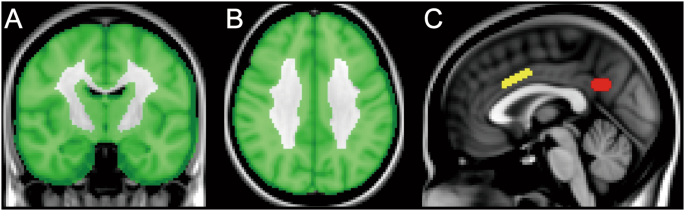

The images were processed using the FMRIB Software Library (version 5.0.4; Oxford University, Oxford, UK). All 18F-FDG images were nonlinearly transformed into the Montreal Neurological Institute (MNI) standard space from the native space using an in-house developed 18F-FDG template. The transformed images were globally normalized using a cortical mask developed in-house as a reference region (Fig. 1A,B). The mean value within the masked voxels was set to 1, and the normalized images were smoothed with an isotropic Gaussian kernel with a sigma of 4 mm for the subsequent voxel-wise and volume-of-interest (VOI) analyses.

Mask and volumes-of-interest (VOIs) on the Montreal Neurological Institute standard brain. A cortical mask was created for the voxel-wise analysis, and is displayed in the coronal (A) and axial (B) sections. The VOIs placed on the anterior cingulate cortex (C: yellow) and posterior cingulate cortex/precuneus (C: red) are displayed in the sagittal section.

A VOI analysis was then performed to test the longitudinal association between 18F-FDG uptake and age, and the influence of ApoE ε4 genotype on 18F-FDG distribution. First, VOIs were manually placed on the ACC and posterior cingulate cortex/precuneus (PCC/PC) in the MNI standard space, where voxel-wise analysis detected highly significant clusters (Fig. 1C). The VOI volumes were 992 mm3 (124 voxels) and 784 mm3 (98 voxels) for the ACC and PCC/PC, respectively. These VOIs were superimposed on normalized 18F-FDG images in the MNI standard space, and the values for the VOIs were extracted. For each of the ACC and PCC/PC VOIs, we also calculated the annual rate of reduction in normalized 18F-FDG uptake (%) as follows: 100 × [(VOI value at baseline) − (VOI value at second PET)]/(VOI value at baseline)/(time interval from baseline to second PET). The annual rates in the ACC and PCC/PC were compared between groups 2 and 3 (i.e., presence or absence of ApoE ε4 genotype) using Student’s t-tests. P values less than 0.05 were considered statistically significant.